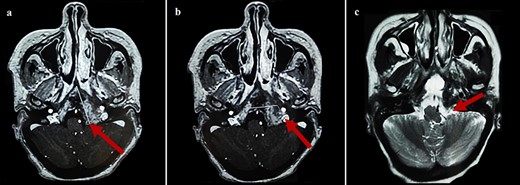

Cerebral computed tomography (CT) revealed a 65-mm hyperdense tumor invading the sphenoid bone and sinus, and eroding the adjacent skull base and clivus. On magnetic resonance imaging (MRI), the tumor appeared isointense on T1 and hypointense on T2-weighted images, showing mild heterogeneous enhancement after gadolinium injection. Local compression and extension to the left cavernous sinus, internal carotid artery, and optic chiasm were observed (Fig. 1).

Cerebral MRI (axial views) showing a 65-mm lesion centered on the sphenoid bone (red arrow) with extension to the internal carotid artery (blue arrow), demonstrating iso-intensity with mild heterogeneous enhancement on T1-weighted (a, b) and hypo-intensity on T2-weighted (c).